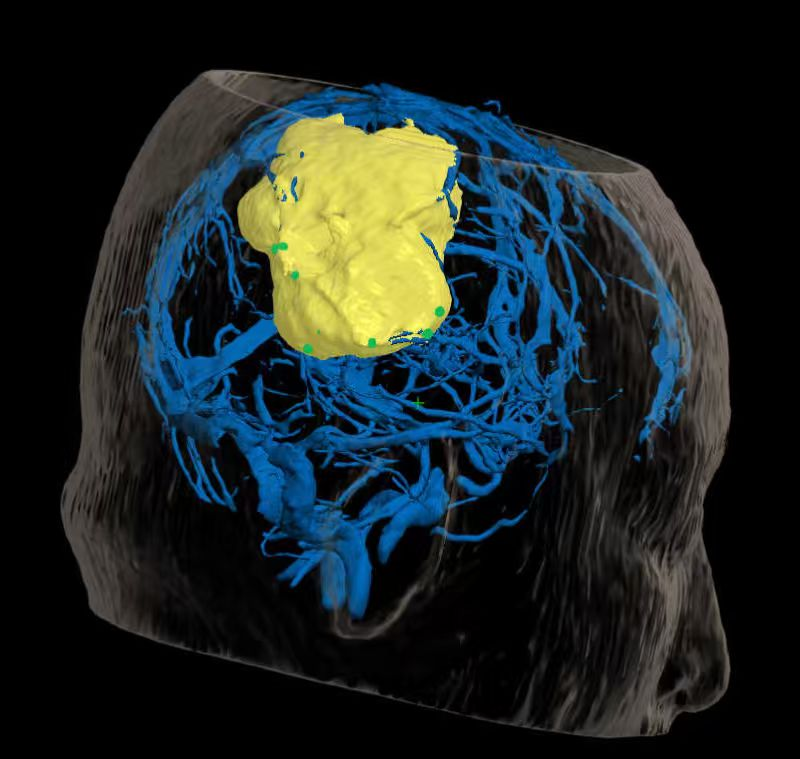

术前精准建模:运用3D Slicer软件整合多模态影像数据重建三维模型,清晰呈现肿瘤与周边功能区、血管的空间关系,为手术规划提供精准数字化依据。

术中实时导航:神经导航系统全程启用,精准匹配术前数据与术中体位,实时定位手术器械位置,成功避开关键功能区及血管,保障操作安全。